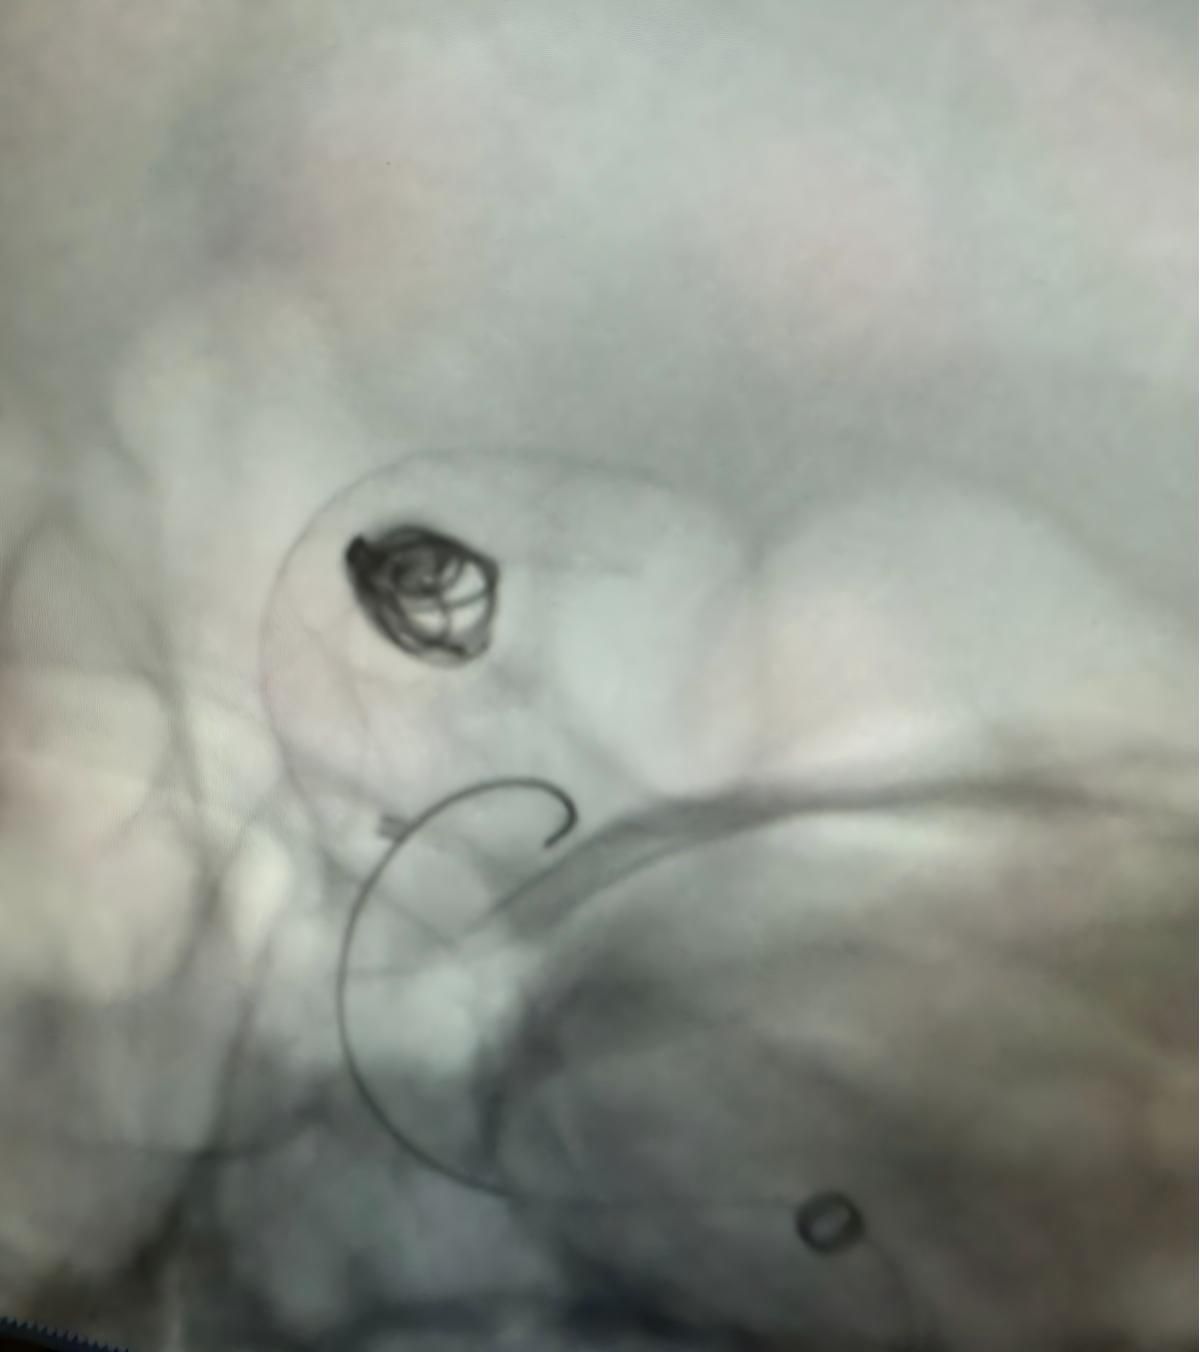

治療はNuvaを利用しました®流れのダイバーター (5.0-14 TJED-D) 、Perdenser®3Dコイル、およびFrepass®後部通信動脈動脈瘤用のマイクロカテーテル (TJMC18 Plus)。

Mutis博士は、デバイスの優れた視認性を強調し、回収がスムーズであると述べました。 彼は最終結果に大きな満足を表明した。